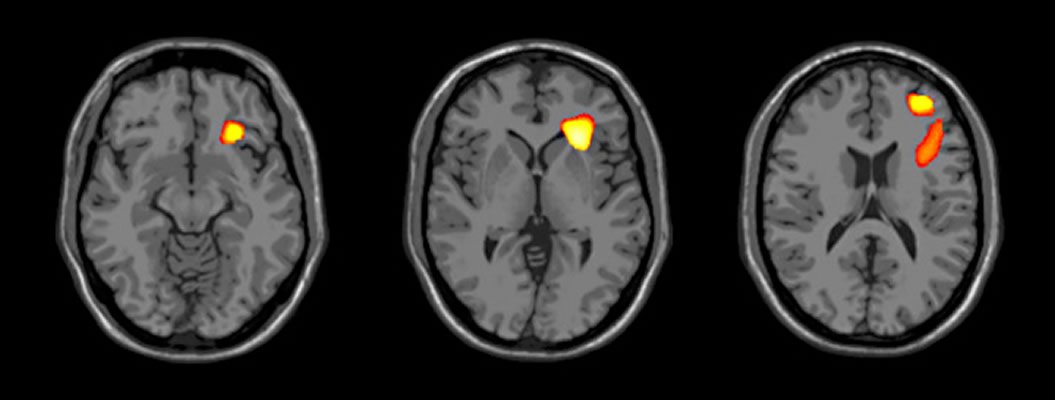

29+ Bipolar Disorder Brain Images Pictures. They found people with bipolar disorder suffer from an accelerated shrinking of their brain. Bipolar disorder, also known as manic depression, is a mental illness that brings severe high and low moods and changes in sleep, energy, thinking, and for example, sometimes it can simply be a matter of genetics, meaning you have it because it runs in your family.

Bipolar disorder is a brain disorder that causes changes in a person's mood, energy, and ability to function. The cause and mechanism of bipolar disorder is not yet known, and the study of its biological origins is ongoing. When you become depressed, you may feel sad or hopeless and lose interest or pleasure in most activities.